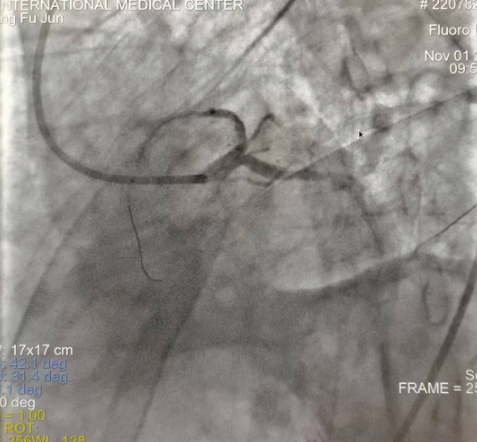

閉塞的血管再通時(shí)間取決于急救時(shí)長(zhǎng)、轉(zhuǎn)運(yùn)時(shí)長(zhǎng)和治療時(shí)長(zhǎng),在前兩方面,醫(yī)院已為患者爭(zhēng)取了最短時(shí)間?;颊呒覍龠h(yuǎn)在陜北,雖然已在趕來(lái)的路上,但最快抵達(dá)西安也要3小時(shí),在與患者家屬電話溝通同意急診手術(shù)后,醫(yī)療總值班代家屬簽字,康曉軍在請(qǐng)示心臟病醫(yī)院王海昌院長(zhǎng)及心臟內(nèi)科CCU尚福軍主任后,積極進(jìn)行術(shù)前準(zhǔn)備。在沒(méi)有家屬陪同、沒(méi)有交費(fèi)、沒(méi)有辦入院手續(xù)的情況下,患者經(jīng)胸痛中心綠色通道被送往心臟冠脈介入手術(shù)室,打通了完全閉塞的心臟前降支近段血管。